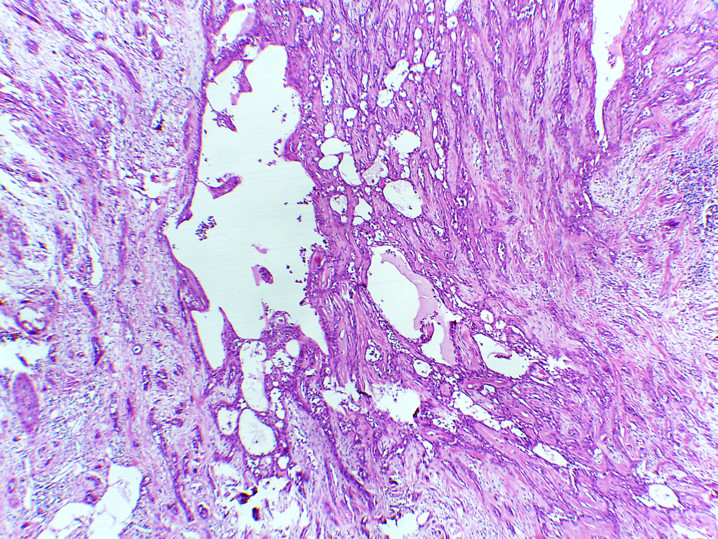

Tumor de células fusiformes con diferenciación semejante a timo (SETTLE por sus siglas en inglés).